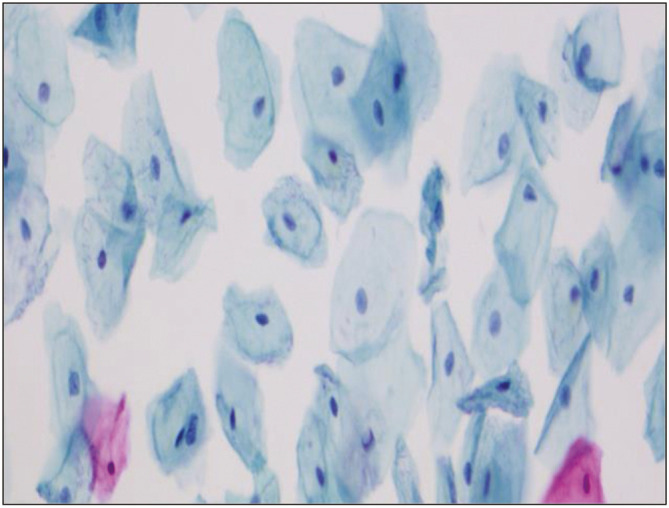

Materials and methods: The present diagnostic study was performed in a tertiary care hospital over a period of 1 year (April 1, 2021-November 30, 2021). A total of 230 women, aged 21-70 years, presented at the gynecology outpatient department for either routine cervical screening or with complaints of vaginal bleeding, discharge, or pelvic pain. Cervical smears were prepared using the Ezi-Prep method and stained with ULTRA-PAP stain.

Results: LBC smears are monolayer smears and are without nuclear overlapping with spread over a diameter of 16 mm. Minimum cellular overlapping and crowding were observed in LBC smears. The mean age of the participants was 35.5 ± 5.1 years. The smears were studied by using nine morphological parameters.